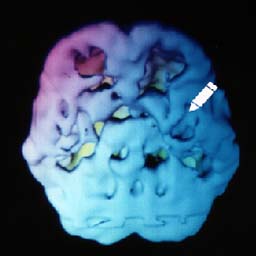

![]() 12 anos de maconha (marijuana) |

O cérebro do usuário de maconha apresenta áreas comidas, especialmente na região do lobo temporal, o lugar da linguagem e do aprendizado. |